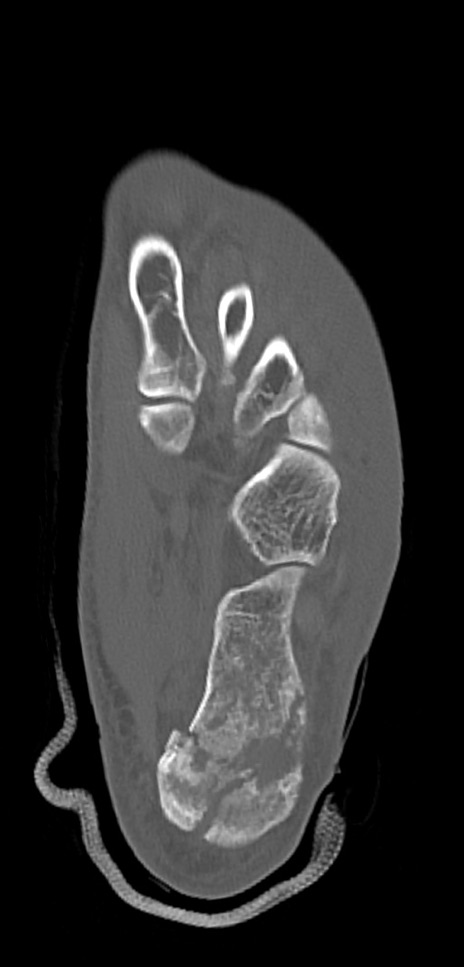

症例37 左足関節CT(横断像)

左足関節CT